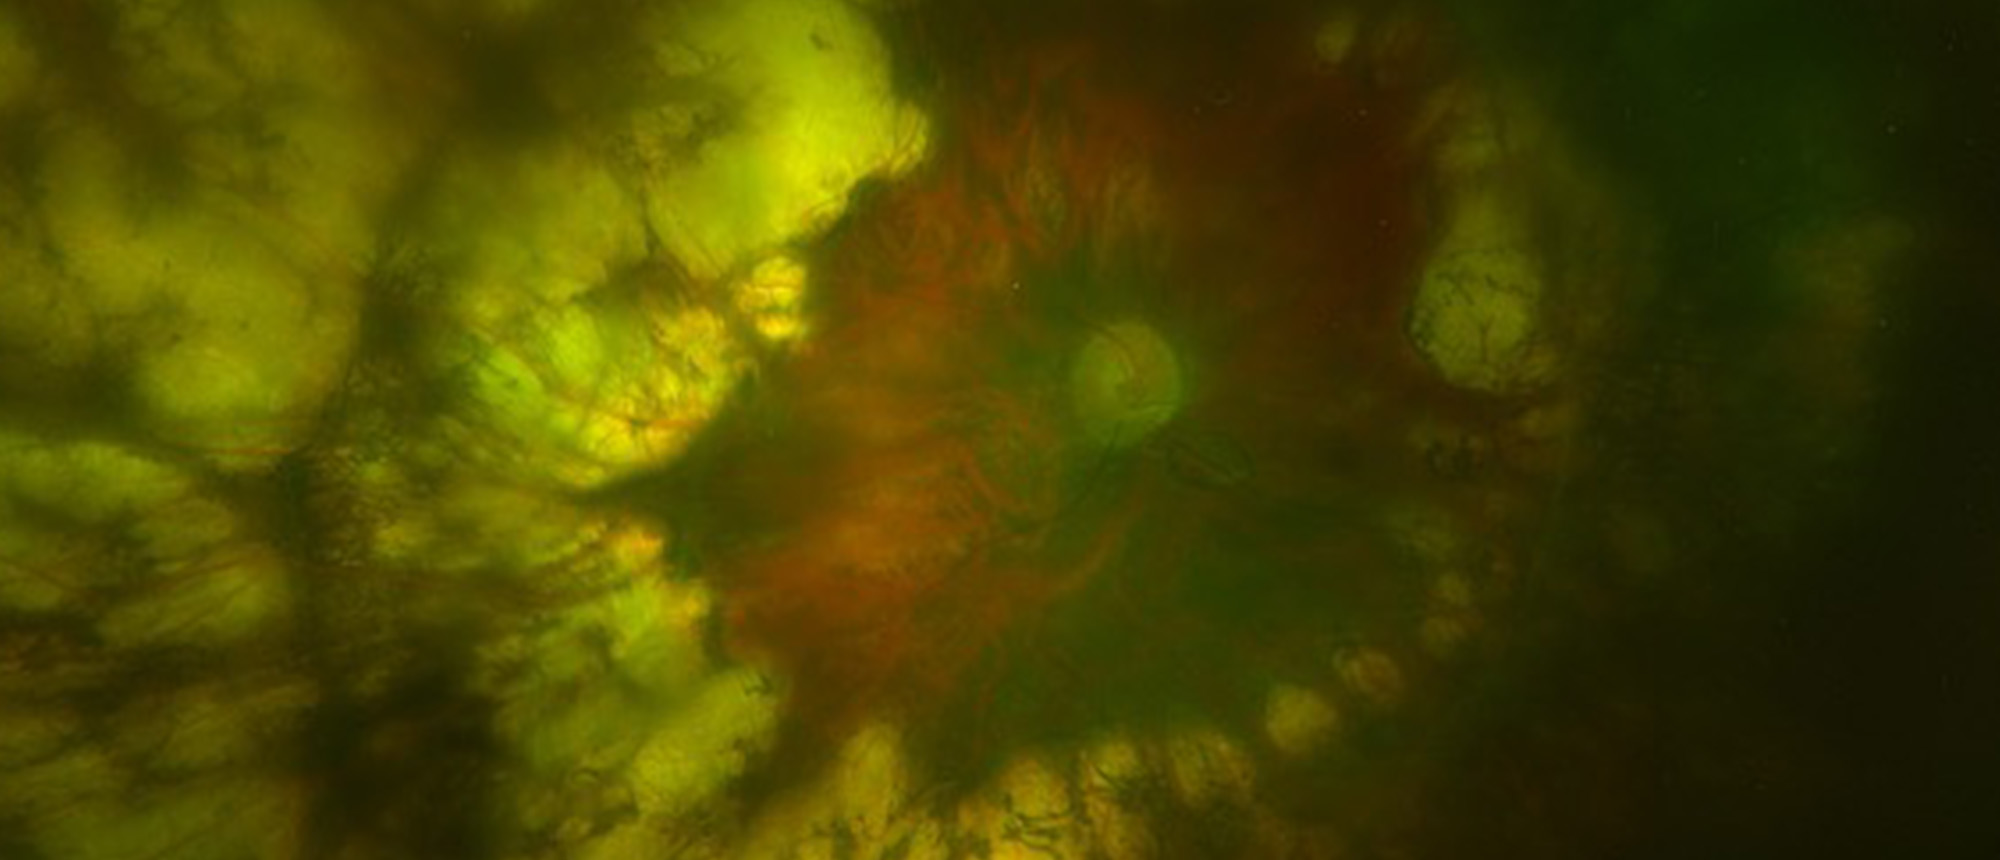

Choroidal Metastasis A patient presented to the Bascom Palmer Eye Institute with blurred vision in the left eye for 5 days. Past medical and ocular history was unremarkable. Past social history was notable for 25 pack-year smoking history. Visual acuity in the right eye was 20/20. Visual acuity in …